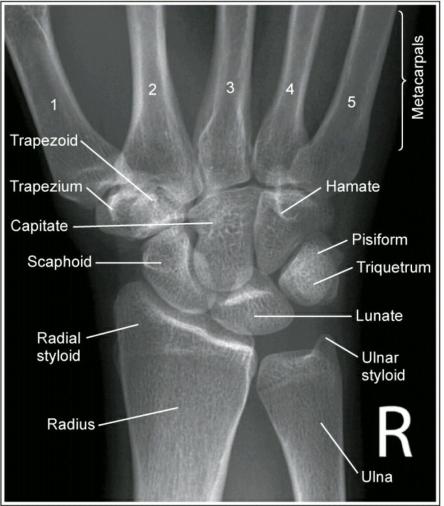

Bones: Get to know these little suckers! The 8 wrist bones have a goofy medical pneumonic “some lovers try positions that they can’t handle” starting with the scaphoid bone (located underneath the thumb). Know these forward and backwards! There are two radio-graphical images of the hand which are important to obtain and used for entirely different purposes. The AP view (front-to-back) is used to visualize joint spacing for dislocations and fractures. A nice symmetrical space or gap should be observed between each bone. As anyone who looks at X-rays all day will tell you, keep looking at normals so the abnormal “jumps out”, which is very much does. Be able to note if there’s been a fracture and which bones are involves. As a heads up if break extends into the joint space the patient’s going to Ortho.